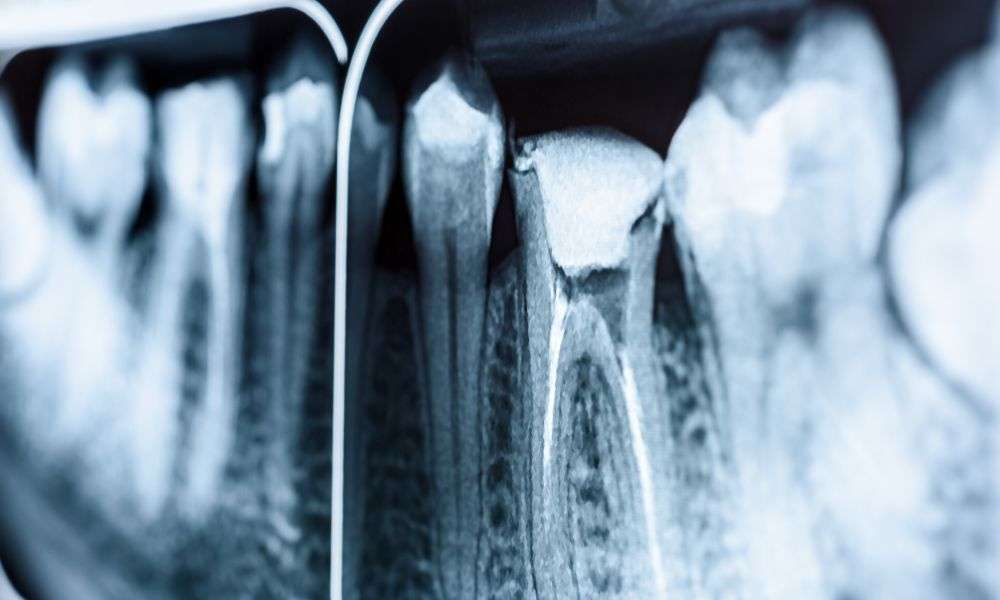

Endodoncia VS extracción dental: ¿Cuál es la mejor opción para salvar tu sonrisa?

Cuando un diente presenta un daño severo, bien sea por caries profundas, traumatismos o infecciones, se deben considerar dos posibles tratamientos: la endodoncia o la extracción dental. Ambos procedimientos tienen como objetivo eliminar el dolor y restaurar la salud bucal, pero se aplican en contextos distintos y con implicaciones diferentes para el paciente. A continuación, […]